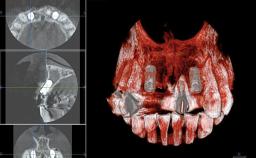

Replacement of Four Incisors with a Fixed Partial Denture on Two Narrow-Neck Implants after Implant Failure

| Jaw | Maxilla |

| Area | Anterior |

| # of Implants | 2 |

| Type of Implants | One-Piece|Reduced-Diameter |

| Bone Volume | Deficient vertically or deficient vertically AND horizontally |